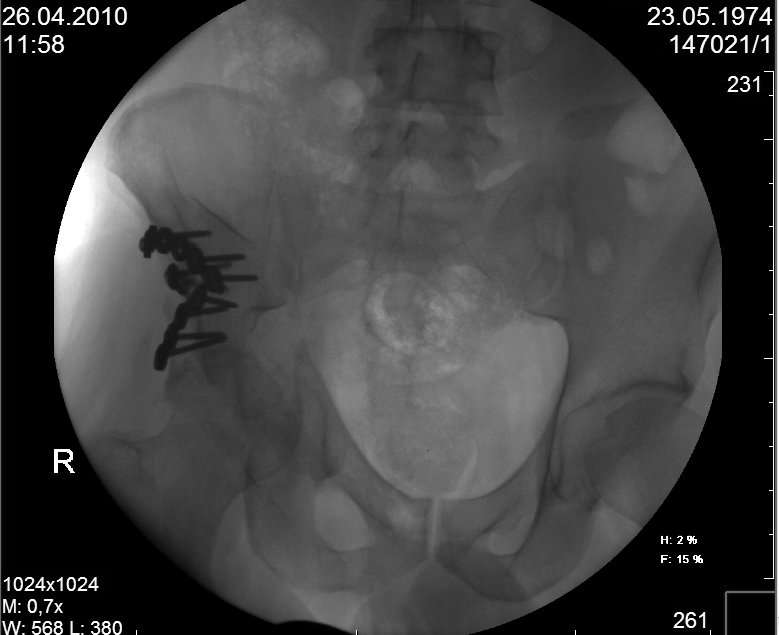

Молодой человек, 35 лет в первых числах января 2010года попал в ДТП, получил перелом правой половины таза.

Был доставлен в одну из ведущих клиник Москвы и прооперирован: была вополнена открытая репозиция и остеосинтез крыла правой подвздошной кости с прилегающей к нему края вертлужной впадины. Но по каким то, мне е понятным соображениям, перелом седалищной кости, проходищая через вертлужную впадину не был отрепонирован ( со слов пациента, доктор сказал что перелом и так срастется).

В настоящее время имеем то что имеем - видно на картинках. Пациент кода то лечился у меня, потому попросил проконсультировать его в создавшейся ситуации.

Мое мнение: пациенту конечно, рано или поздно, предстоит эндопротезирование правого тазобедреного сустава. Но хотелось бы вертлужный компонент поставить в более сформированню вертлужную впадину, чем сейчас имеется.